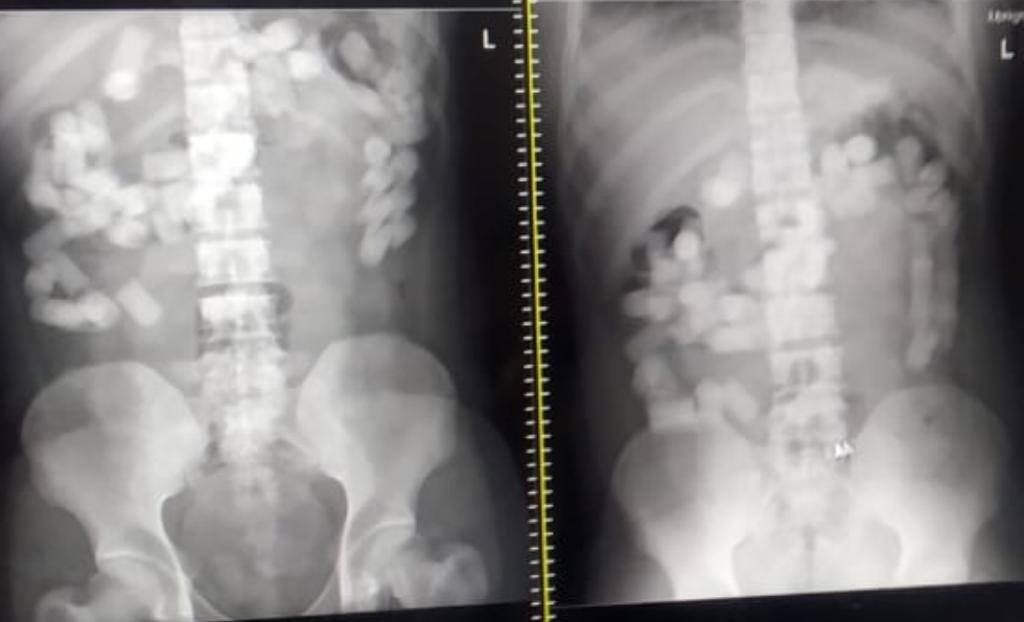

ਨਵੀਂ ਦਿੱਲੀ: ਅੱਜ ਨਾਰਕੋਟਿਕਸ ਕੰਟਰੋਲ ਬਿਊਰੋ ਨੇ ਅੰਤਰਰਾਸ਼ਟਰੀ ਡਰੱਗ ਸਿੰਡੀਕੇਟ ਦਾ ਪਰਦਾਫਾਸ਼ ਕਰਦੇ ਸੱਤ ਅਫ਼ਗਾਨੀਆਂ ਨੂੰ ਗ੍ਰਿਫਤਾਰ ਕੀਤਾ ਹੈ। ਨਾਰਕੋਟਿਕਸ ਡਿਪਾਰਮੈਂਟ ਨੇ ਇਨ੍ਹਾਂ ਨਸ਼ਾ ਤਸਕਰਾਂ ਨੂੰ ਨਵੀਂ ਦਿੱਲੀ ਹਵਾਈ ਅੱਡੇ ਤੋ 1 ਕਿਲੋ 623 ਗ੍ਰਾਮ ਹੈਰੋਇਨ ਨਾਲ ਕਾਬੂ ਕੀਤਾ ਹੈ। ਹੈਰਾਨੀ ਵਾਲੀ ਗੱਲ ਇਹ ਹੈ ਕਿ ਇਨ੍ਹਾਂ ਸੱਤਾਂ ਨੇ ਇਹ ਹੈਰੋਇਨ ਦੇ ਕੈਪਸੂਲ ਪੇਟ 'ਚ ਲਕੋਏ ਸੀ ਜਿਸ ਦੀ ਪੁਸ਼ਟੀ ਡਾਕਟਰੀ ਜਾਂਚ ਦੌਰਾਨ ਹੋਈ। ਡਾਕਟਰਾਂ ਨੇ ਐਕਸ-ਰੇ ਰਾਹੀਂ ਪੇਟ 'ਚ ਕੈਪਸੂਲਾਂ ਦੀ ਮੌਜੂਦਗੀ ਦੀ ਪੁਸ਼ਟੀ ਕੀਤੀ। ਨਾਰਕੋਟਿਕਸ ਕੰਟਰੋਲ ਬਿਓਰੋ ਨੋਡਲ ਡਰੱਗ ਲਾਅ ਇਨਫੋਰਸਮੈਂਟ ਤੇ ਇੰਡੀਆ ਦੀ ਖੁਫੀਆ ਏਜੰਸੀ ਹੈ ਜੋ ਨਸ਼ਾ ਤਸਕਰੀ ਤੇ ਗ਼ੈਰਕਾਨੂੰਨੀ ਪਦਾਰਥਾਂ ਦੀ ਦੁਰਵਰਤੋਂ ਵਿਰੁੱਧ ਲੜਨ ਲਈ ਜ਼ਿੰਮੇਵਾਰ ਹੁੰਦੀ ਹੈ।